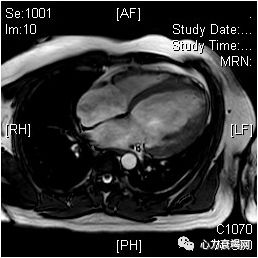

心脏核磁

左室明显扩大

左室各壁厚度大致正常

左室心尖部非致密化心肌/致密化心肌>2.3

各节段收缩运动均明显减弱

心肌首过灌注及延迟增强未见明确异常信号

右房室大致正常,右室流出道饱满,肌小梁明显增多

主肺动脉无扩张

二、三尖瓣及主动脉瓣活动大致正常

心包无增厚,未见明显胸腔积液左室EF值 25%,CO4.1L/min

扩张型心肌病可能性大